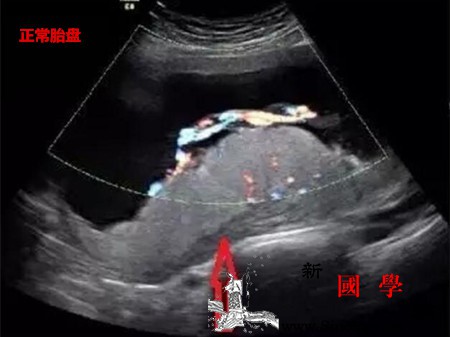

胎盘早剥超声表现_血肿-胎盘-回声-附着-